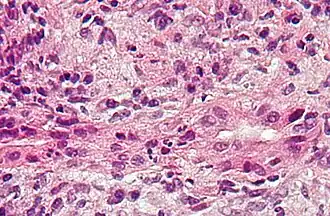

Una hepatopatía previa no diagnosticada se puede detectar tras la autopsia. Abajo se muestran imágenes de la patología:

-

Cirrosis difusa -

Cirrosis macronodular -

Textura de nuez moscada de la hepatopatía congestiva -

Metástasis hepáticas